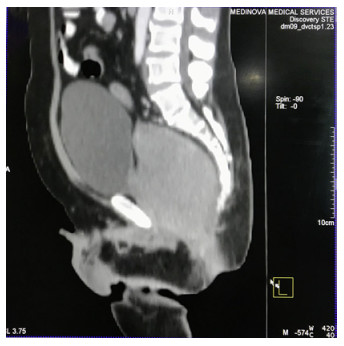

Abstract: Rectal malignancy is usually symptomatic due to its location, and most of the time presents with pain and bleeding due to its growth and ulceration. It is difficult to identify the primary as carcinoma or lymphoma based on symptoms only, as both have a similar presentation. As it presents the rarest form of histology, non-Hodgkin's lymphoma in the rectum is still difficult to diagnose initially, and its treatment is debatable. We describe the case of a 49-year-old male from Bangladesh with the same presentation. His treatment was delayed for more than a month as immunohistochemistry and staging delayed the final diagnosis. The disease was diagnosed as stage IE with the help of a positron emission tomography (PET)-CT scan, and due to the local progression the patient had a massive rectal bleeding that needed an urgent intervention. Radiotherapy was applied to stop the bleeding. Hypofraction followed by a conventional fraction of external beam radiotherapy (EBRT) with a total of 40 Gy was applied. Post-EBRT digital rectal examination showed no residual except scaring, and a PET scan was also negative for residual disease. Due to uncertainties and lack of any precious guideline, 6 cycles of adjuvant chemotherapy with the R-CHOP schedule were also completed. Without surgery, the combination of EBRT and chemotherapy helped to preserve the organ, and the patient has been disease free for more than 2.5 years since his treatment.